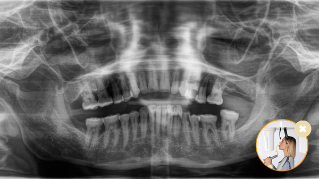

Il risultato: scansioni precise grazie al morso occlusale

Posizionamento corretto del paziente con il morso occlusale - inclinazione ideale garantita per le immagini panoramiche

Posizionamento del paziente non corretto - paziente inclinato in avanti

Posizionamento del paziente non corretto - paziente inclinato all'indietro